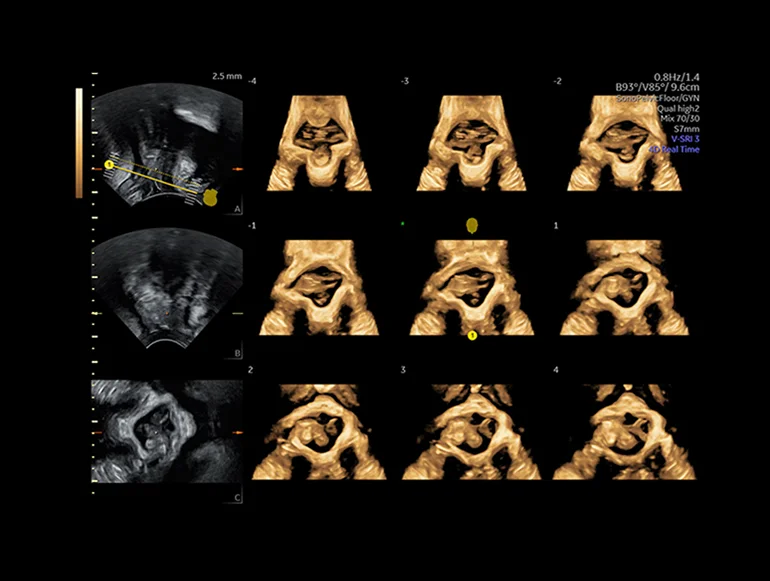

Тазовое дно (серия плоскостей), визуализированное с помощью функции SonoPelvicFloor на основе ИИ

Трехмерный режим — дальнейшее развитие В-режима. Объемное трехмерное изображение достигается путем компьютерного преобразования сигнала, полученного при помощи датчика с изменяющейся плоскостью излучения. Данный метод позволяет получить объемное изображение органа и исследовать его в различных проекциях. Особенно информативным он оказался в пренатальной диагностике врожденных аномалий развития плода. В ультразвуковых приборах экспертного и высокого классов имеется режим трехмерной энергетической доплерографии или трехмерной ультразвуковой ангиографии. Прибором реконструируется трехмерное изображение только цветовой части эхограммы, характеризующей кровоток в сосудах. Меняя ракурс наблюдения, поворачивая трехмерное изображение сосудов, получают представление о пространственном расположении и форме сосудов, что дает дополнительную диагностическую информацию.